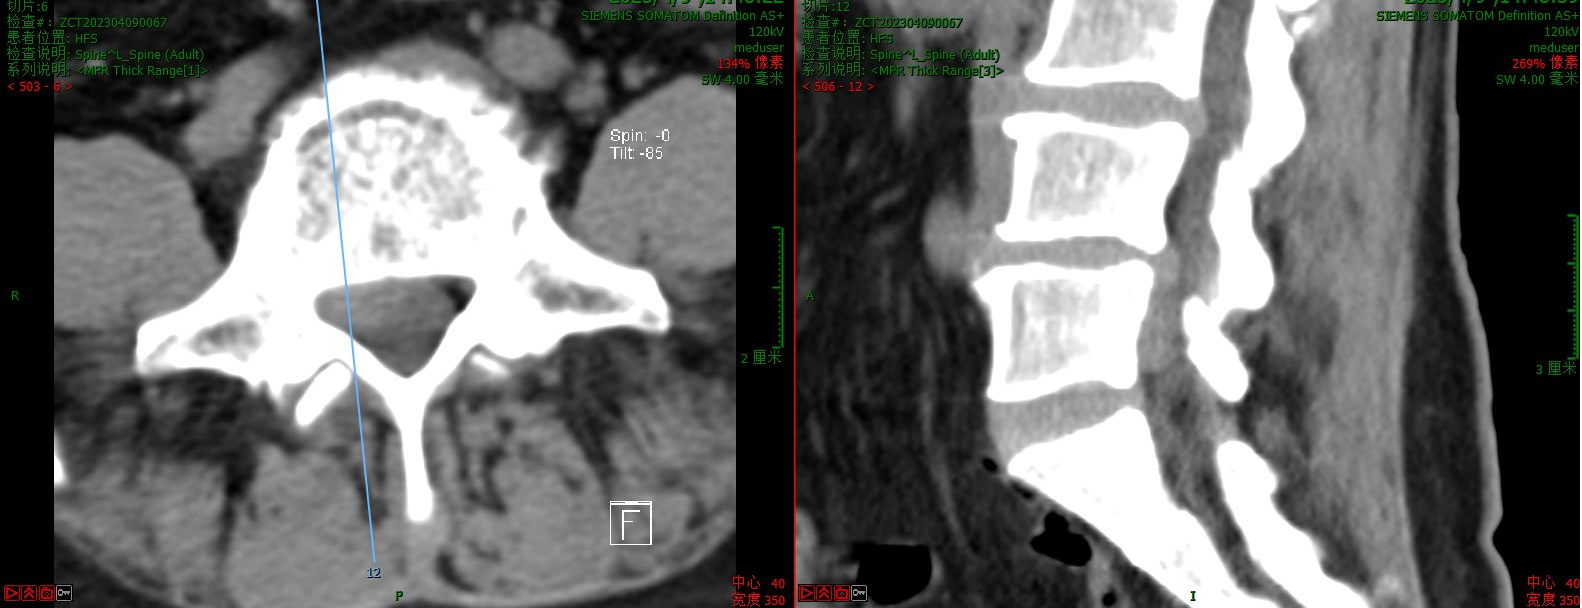

第一例病例为一名中年男性,腰4/5椎间盘突脱出并向下游离接近腰5/骶1椎间隙,为其实施VBE内镜下突出髓核单纯摘除术。患者术前腰痛伴右下肢疼痛麻木1个月余,右拇指背伸肌力明显下降。术后疼痛完全缓解,肌力较前部分恢复,有轻度麻木。

术前CT